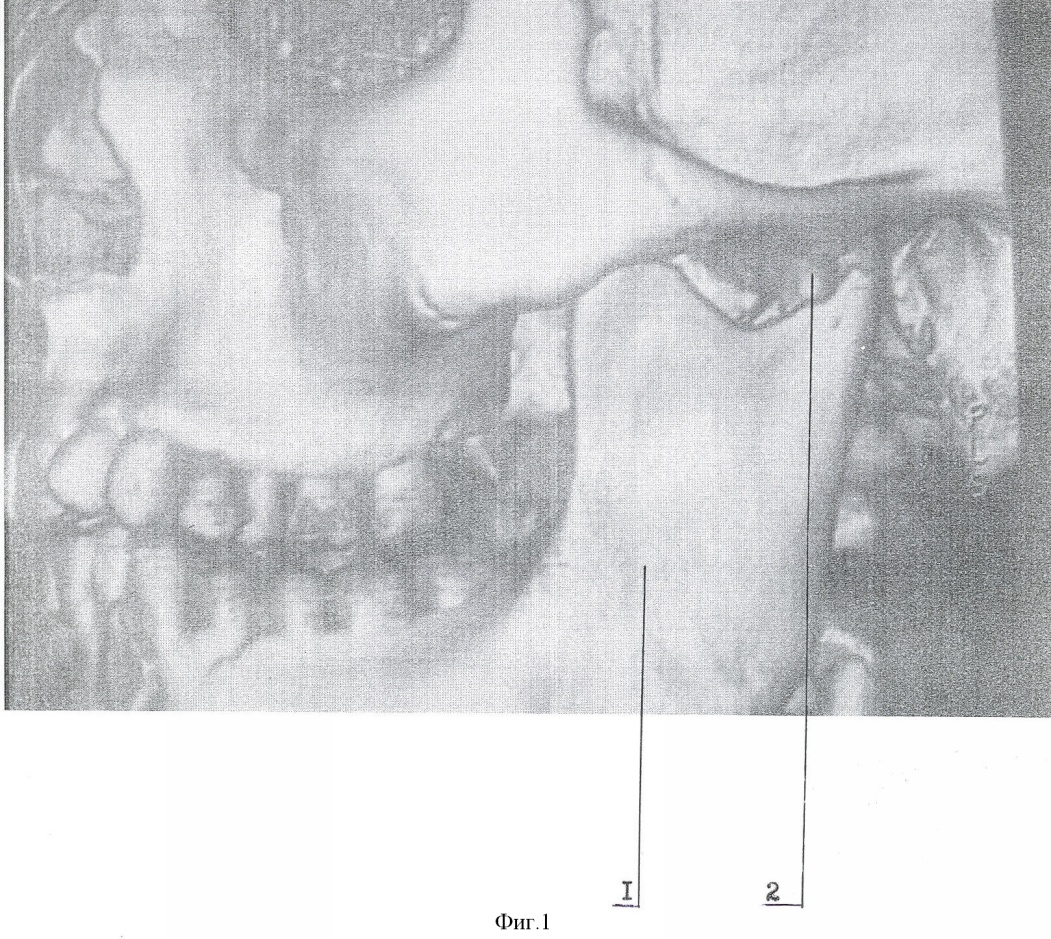

Способ осуществляют следующим образом. Типичным доступом через разрез кожи в подчелюстной области, окаймляющим угол нижней челюсти, осуществляют послойный доступ к линии перелома поднадкостнечно по латеральной поверхности ветви. Вывихнутый диссектором малый фрагмент вместе с суставной капсулой выводят в вырезку. Суставную капсулу рассекают вперед на 0,3-0,5 см. Отломок суставного отростка освобождают от суставной капсулы и выводят из раны. Фиброзные наложения раневых поверхностей костей удаляют. После оценки состояния отломка к участку, свободному от суставной поверхности, по заднему краю фиксируют микропластину (Т, Н, Х, L, Y-образной формы). Свободный конец микропастины изгибают для плотного прилегания к большему фрагменту по задней и латеральной поверхности ветви. Из суставной капсулы формируют ложе в суставной впадине. Малый фрагмент с подготовленной микропластиной устанавливают в ложе в анатомическом положении. Суставную капсулу над суставным бугорком укрепляют узловыми швами ПДС 4/0. Большой фрагмент репонируют на установленную в ложе конструкцию. Свободный конец микропластины фиксируют к заднелатеральной поверхности большего фрагмента микрошурупами. Осуществление способа и результат продемонстрированы на чертежах 1-8: фиг.1 – компьютерная томограмма (реконструкция) нижней челюсти, левая боковая; фиг.2 – компьютерная томограмма (реконструкция) нижней челюсти, вид сзади; фиг.3 – компьютерная томограмма (реконструкция) нижней челюсти, вид косо сзади; фиг.4 – собранная конструкция, вид сзади; фиг.5 – собранная конструкция, вид спереди; фиг.6 – компьютерная томограмма (реконструкция), вид спереди, после операции; фиг.7 – компьютерная томограмма (реконструкция) нижней челюсти, левая боковая, после операции; фиг.8 – компьютерная томограмма (реконструкция) нижней челюсти, левый суставной отросток, вид изнутри, после операции: где 1 – нижняя челюсть, 2 – отломок суставного отростка, 3 – титановая микропластина, 4 – микрошуруп, 5 – дренажная трубка.

Пример. Больной П., 14 лет поступил в отделение челюстно-лицевой хирургии ДККБ 20.04.07 г. с диагнозом: травматический тройной перелом нижней челюсти; перелом – вывих головки суставного отростка слева, перелом суставной головки справа без смещения, косой центральный перелом тела нижней челюсти со смещением (фиг. 1, 2, 3). 23.04.07 г. под общим обезболиванием выполнено оперативное вмешательство – открытая репозиция, металлоостеосинтез суставной головки слева Т-образной микропластиной, открытая репозиция, металлоостеосинтез косого перелома тела нижней челюсти двумя параллельными минипластинами. Типичным доступом через разрез кожи в подчелюстной области слева, окаймляющим угол нижней челюсти 1, осуществлен послойный доступ к линии перелома поднадкостнечно по латеральной поверхности ветви нижней челюсти. При помощи диссектора малый фрагмент мобилизован и вывихнут в вырезку вместе с суставной капсулой. Суставная капсула рассечена вперед на 0,5 см. Отломок суставного отростка 2 освобожден от суставной капсулы и выведен наружу. Фиброзные наложения на раневых поверхностях фрагментов удалены. По заднему краю отломка, по поверхности, свободной от суставной, при помощи микрошурупов 4 фиксирована Т-образная титановая микропластина 3, изогнутая для плотного прилегания к заднелатеральной поверхности большего фрагмента (фиг. 4, 5). Суставная капсула перемещена и расправлена в суставной ямке. В образованное ложе уложена конструкция в анатомическом положении. На края суставной капсулы над суставным бугорком наложены 2 узловых шва ПДС 4/0, обеспечивающие плотный охват отломка. Больший фрагмент репонирован на установленную конструкцию. Свободный конец микропластины 4 после небольшой коррекции изгиба фиксирован к заднелатеральной поверхности большего фрагмента микрошурупами 3. Рана послойно ушита с оставлением активного дренажа 5. Подчелюстным разрезом осуществлен послойный доступ к линии перелома тела нижней челюсти. Произведена типичная репозиция костных отломков, остеосинтез двумя параллельными минипластинами. Рана послойно ушита.

В послеоперационном периоде проводилась иммобилизация челюсти при помощи шин Васильева с межчелюстными вытяжениями. На контрольно компьютерной томограмме (26.04.07 г., фиг. 6, 7, 8) выявлено удовлетворительное стояние костных отломков. Больной выписан 4.05.07 г на дальнейшее амбулаторное лечение.